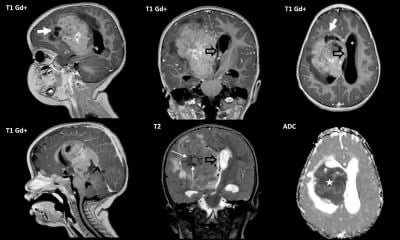

High-grade gliomas are aggressive brain tumors that can strike at any age, but in infants, they have historically carried a grim prognosis—often limiting life expectancy to just two years or less. These tumors grow rapidly in the developing brain, causing symptoms like irritability, vomiting, enlarged head size, and developmental delays.

Dr. Clarke’s research, part of an international collaboration, pinpointed a molecular subgroup of these tumors occurring exclusively in infants under 12 months. This subgroup features distinct genetic markers that make the cancer cells vulnerable to already-approved targeted therapies—drugs originally developed for other cancers.

The study, contributing to a new chapter in the World Health Organization’s classification of brain tumors, involved detailed genomic analysis of infant gliomas. Researchers found that this subgroup lacks the aggressive features seen in older children and adults, responding instead to precision medicines that block specific cancer-driving pathways.